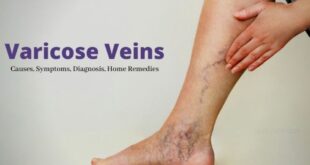

पैरों की नसों में बदलाव? जानें वैरिकोज वेन्स की शुरुआत कैसे होती है

वैरिकोज वेन्स, यानी पैरों की नसों का फूला हुआ या उभरा होना, महिलाओं और पुरुषों दोनों में आम समस्या बनती जा रही है। शुरुआती समय में इसे नजरअंदाज करना बाद में पैरों की दर्द, सूजन और थकान जैसी समस्याओं का कारण बन सकता है। वैरिकोज वेन्स की शुरुआती लक्षण: पैरों में भारीपन या थकान दिनभर खड़े रहने या चलने के …